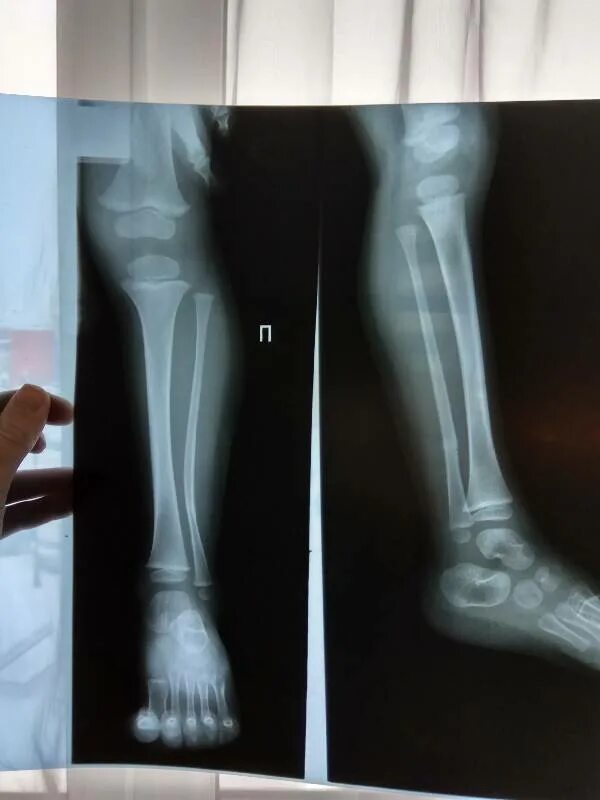

Трещина в кости ноги сколько